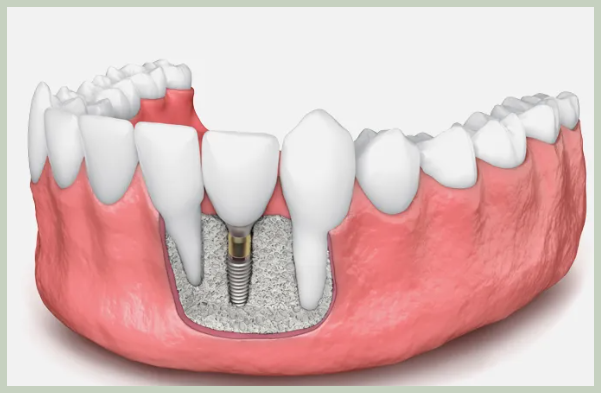

임플란트는 자연치아를 대체하는 가장 효과적인 치료법 중 하나이지만, 임플란트를 식립 하기 위해서는 잇몸 뼈가 충분해야 합니다. 하지만 치주 질환, 외상, 노화 등으로 인해 잇몸 뼈가 부족한 경우 임플란트 식립이 어려울 수 있습니다. 😥 이때 필요한 것이 바로 뼈이식입니다.

뼈이식은 부족한 잇몸 뼈를 보충하여 임플란트 식립을 가능하게 하는 시술입니다. 뼈이식 재료는 환자 본인의 뼈, 동물의 뼈, 인공 뼈 등 다양하며, 환자의 상태에 따라 적절한 재료를 선택하여 사용합니다.

2. 치아 뼈이식 과정, 어떻게 진행될까요? 💉

- 뼈이식 재료 삽입: 선택된 뼈이식 재료를 부족한 잇몸 뼈 부위에 삽입합니다.

- 임플란트 식립: 뼈이식 후 잇몸 뼈가 충분히 단단해지면 임플란트를 식립 합니다.